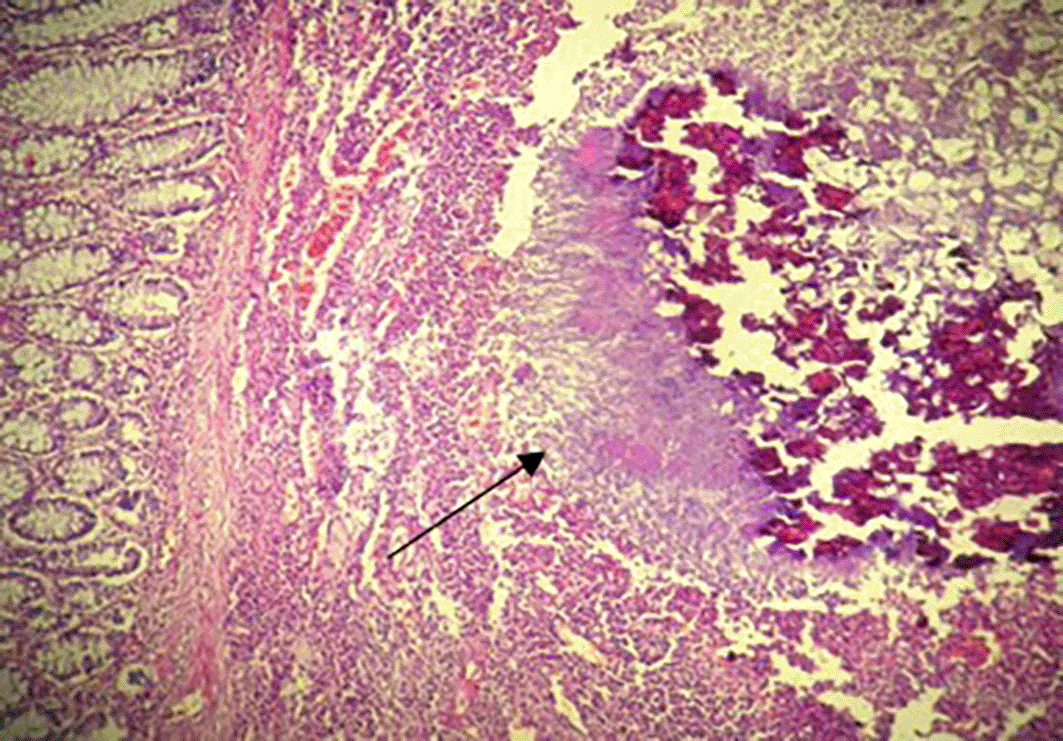

A 68-year-old Tunisian man, with a history of diabetes, hypertension, penicillin allergy, and renal failure, with no prior surgical history, presented to the emergency department with abdominal pain, vomiting, and bowel obstruction. The patient reported a similar symptomatology over the last two months, which resolved spontaneously. He also complained of chronic abdominal discomfort. On examination, he was hemodynamically stable. There was no fever. The abdominal examination revealed a distended and resonant abdomen, tender throughout, with a palpable mass in the left iliac fossa. The laboratory tests were normal, except for a previously known renal failure. We followed up with an abdominal CT scan without contrast, which revealed an acute intestinal obstruction upstream of a suspected obstructive tissue process at the sigmoid colon, with associated satellite lymph nodes and a dilated cecum measuring 12 cm (Figure 1). Emergency surgery was decided after a brief resuscitation. Exploration of the abdomen by midline laparotomy revealed a mass in the sigmoid loop, measuring 7 cm along its major axis, adherent to the omentum, the parietal peritoneum, and the posterior wall, with dilation of the entire upstream colonic frame. The cecum was dilated to 13 cm with a weakened, pre-perforative wall. We underwent a total colectomy with ileostomy and distal end closure (Figure 2). The postoperative recovery was uneventful. Gross pathologic examination of the surgical specimen revealed a stenosing lesion of the sigmoid colon with ulcerated surface mucosa. Histological examination showed acute inflammatory reaction and abscess formations surrounding clumps of short branching basophilic filaments stained with PAS (Periodic Acid Schiff). Dense fibrosis was associated. There was no granulomatous inflammation (Figures 3, 4). Actinomyces infection was confirmed. The patient was then placed on long-term doxycycline and Bactrim. Upon follow-up, he was seen regularly for 9 months. No recurrence has been diagnosed. The restoration of bowel continuity was postponed until completing a full year of antibiotic therapy.